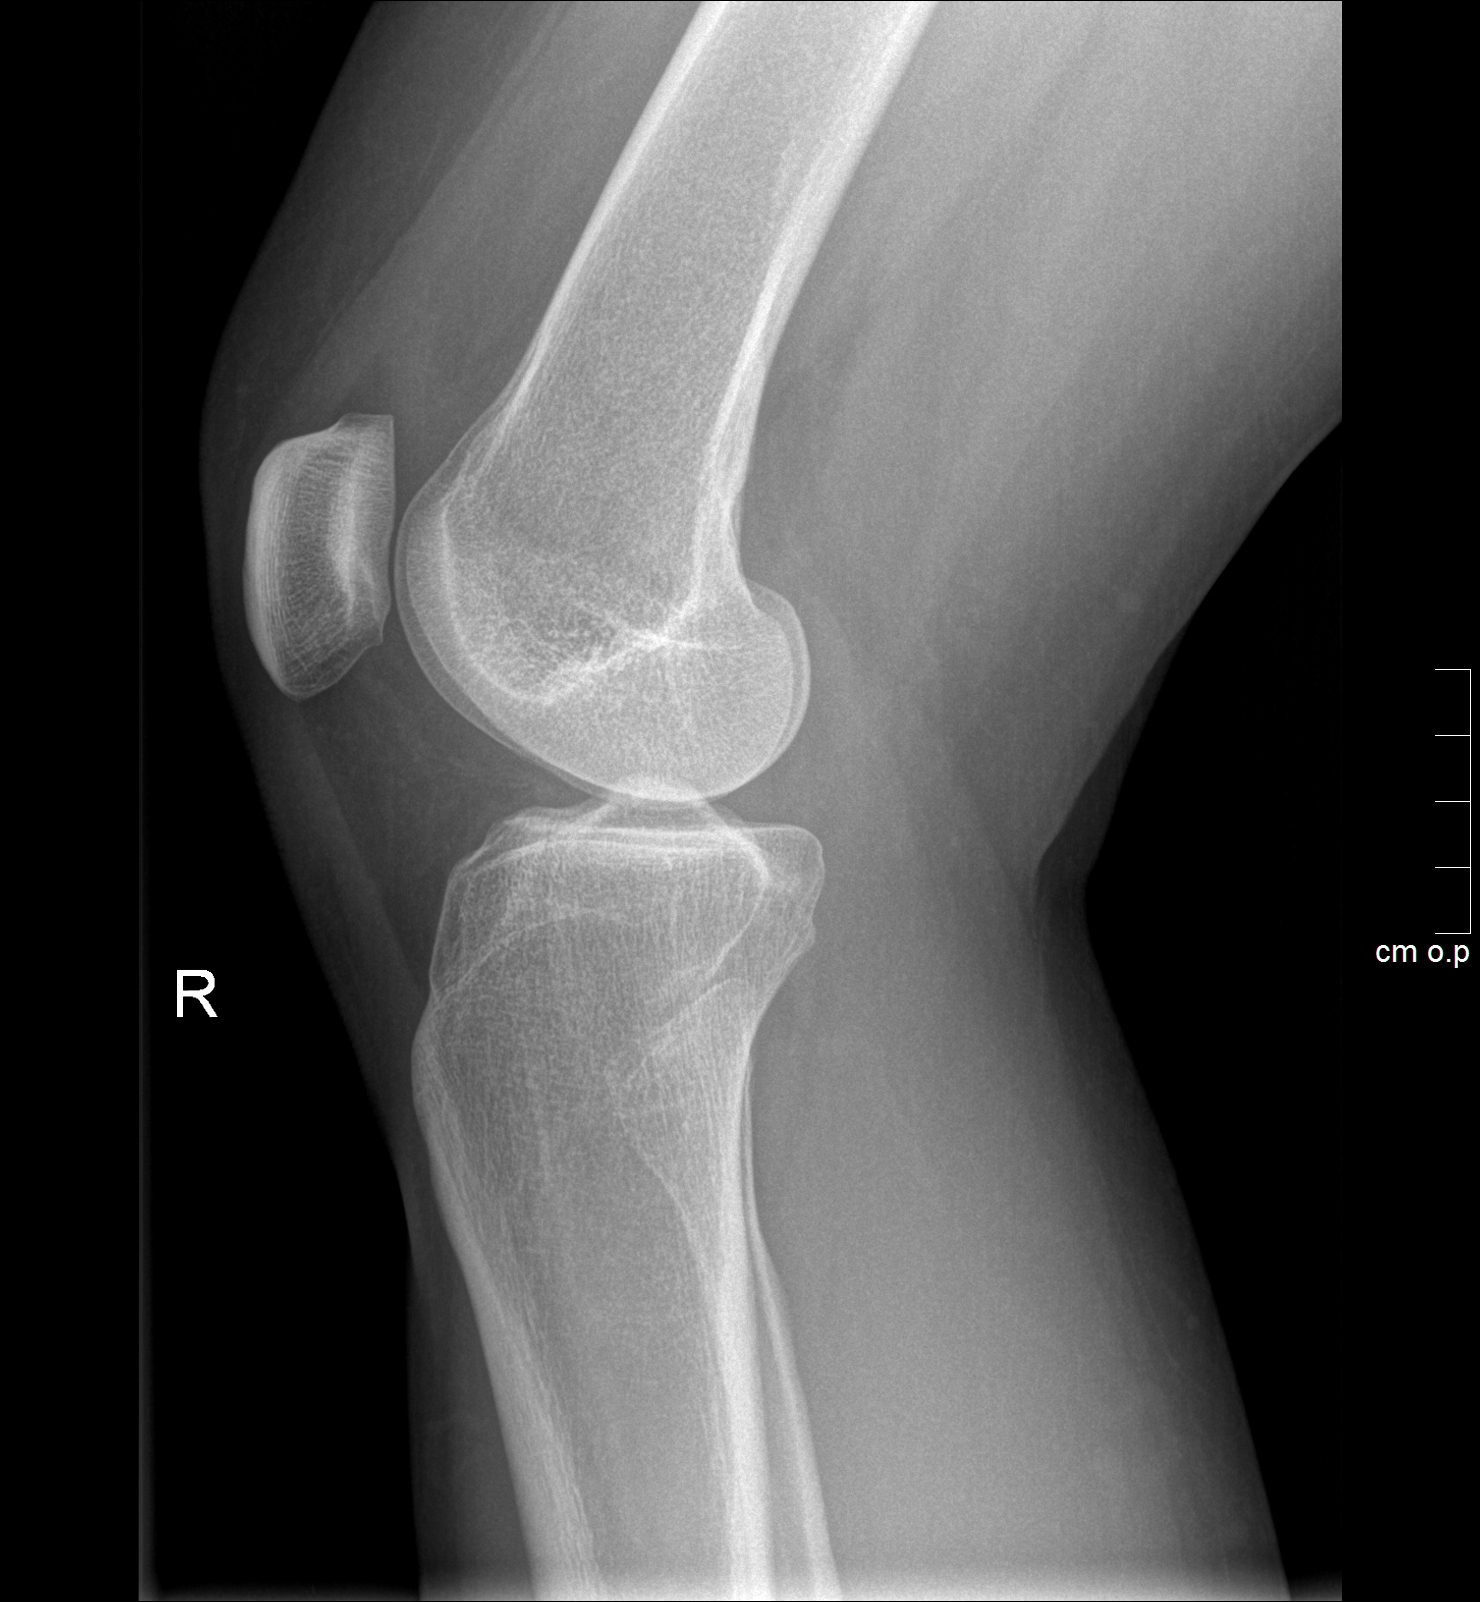

• Alle Röntgenaufnahmen des Skelettes inklusive orthopädische Spezialaufnahmen

• Aufnahmen nach Verletzungen